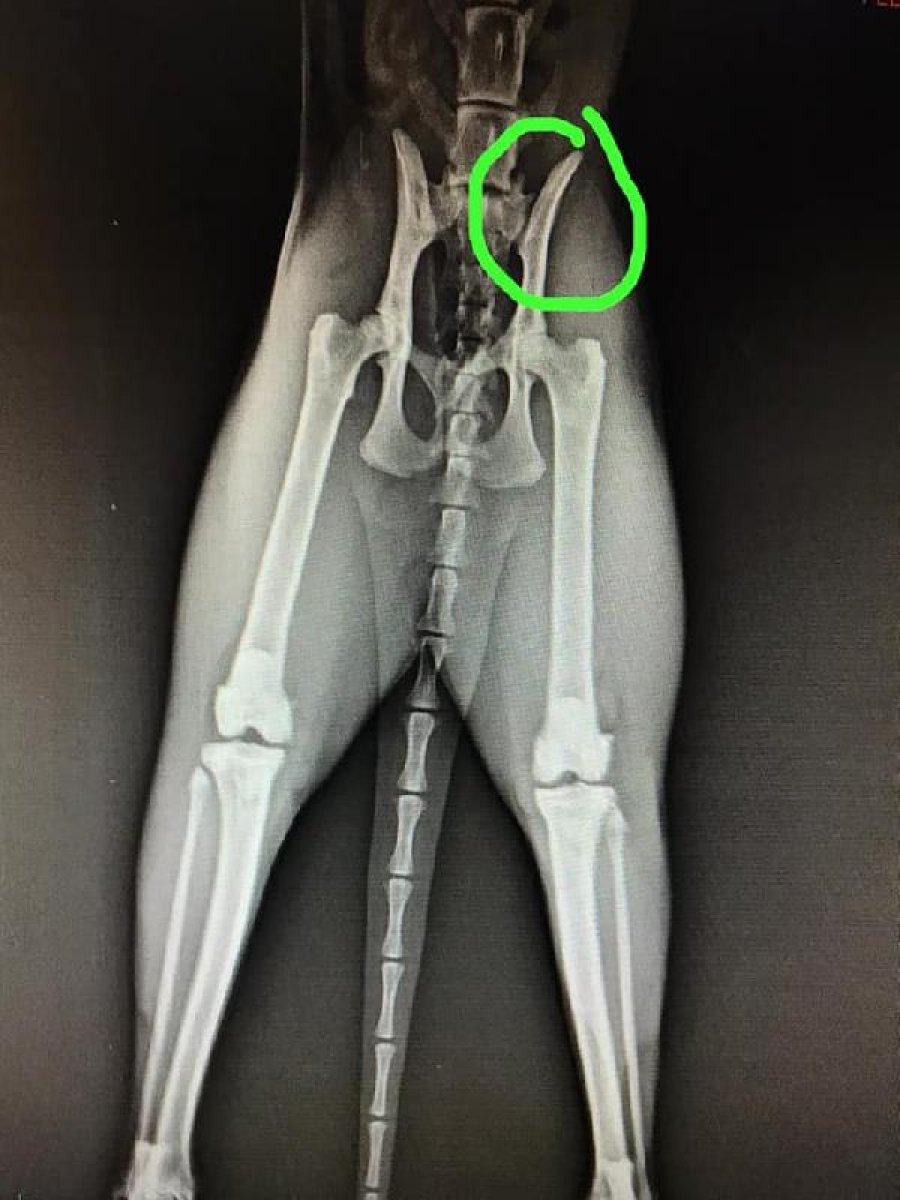

Görüntüler, sosyal medyada paylaşılmasının ardından büyük tepki gördü. Eskişehir Hayvanları Koruma Derneği Başkanı Gülçin Yapıcı, kedinin kurtarıldığını ifade ederek, "Kedimizin bacağında çatlağı varmış. Kedinin tedavisini de yaptırmışlar ve şükür artık güvende. Dernek olarak da şikayette bulunduk. Eskişehir Emniyet Müdürlüğü kişiyi yakaladı ve adli işlemlere başlandı. Yine de başka canların zarar görmemesi adına lütfen bu kişiye karşı dikkatli olalım. Sahipsiz bir canı daha alıp, şiddete maruz bırakmasın." dedi.